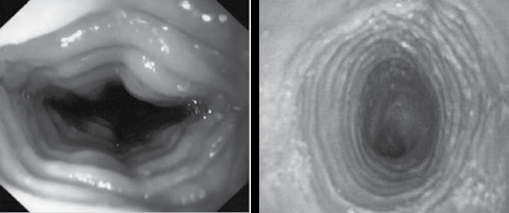

Observe as imagens a seguir.

É correto afirmar que as imagens são sugestivas de